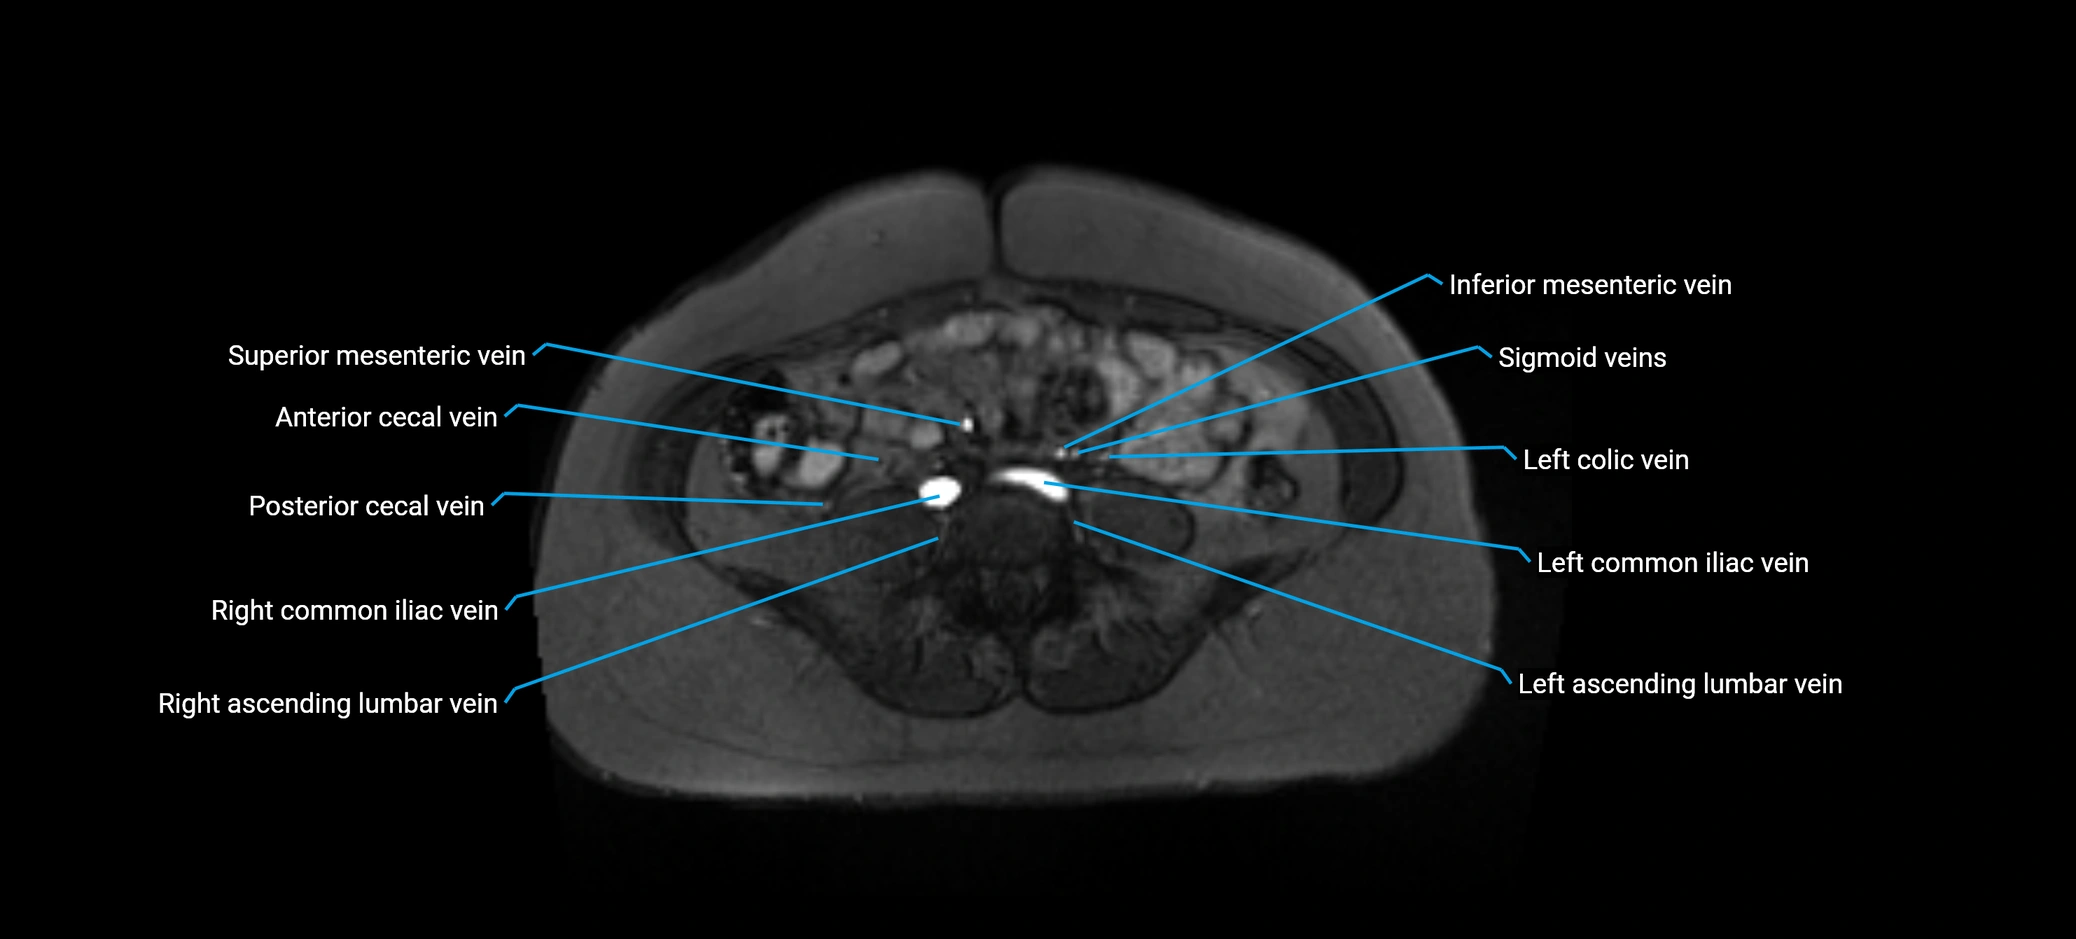

MRI image

image